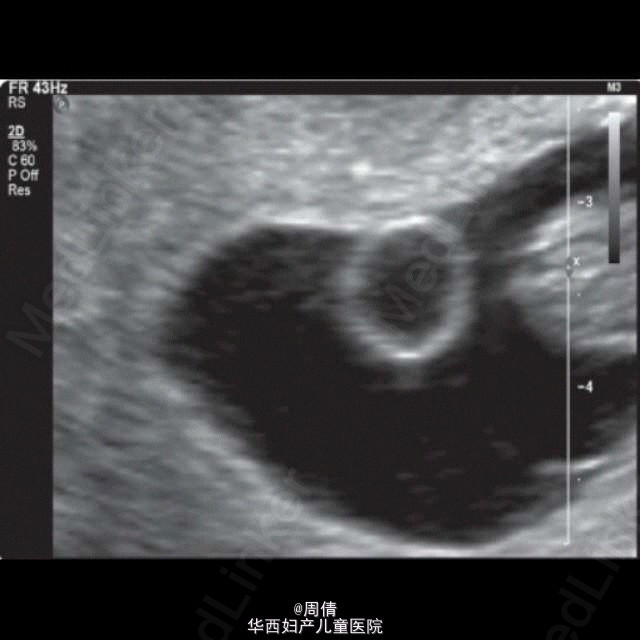

超声诊断单绒毛膜双胎羊膜囊融合一例

37岁女性,G3P1,自然受孕9w。 阴道超声示:子宫腔单个妊娠囊内2个胎儿,单绒毛膜。拥有共同的卵黄囊,在脐周相互连接。